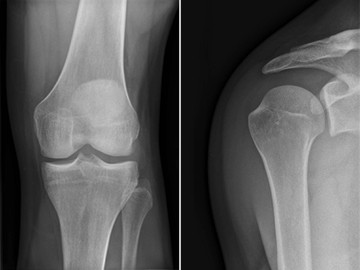

- Diagnostik: Präzise Bildgebung von Bewegungsapparat, Knochen, Gelenken und Weichteilen mittels MRT, CT und Röntgen.